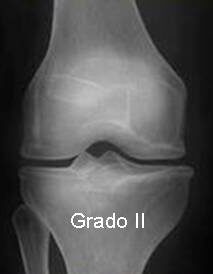

- Radiografías para evaluar el espacio articular